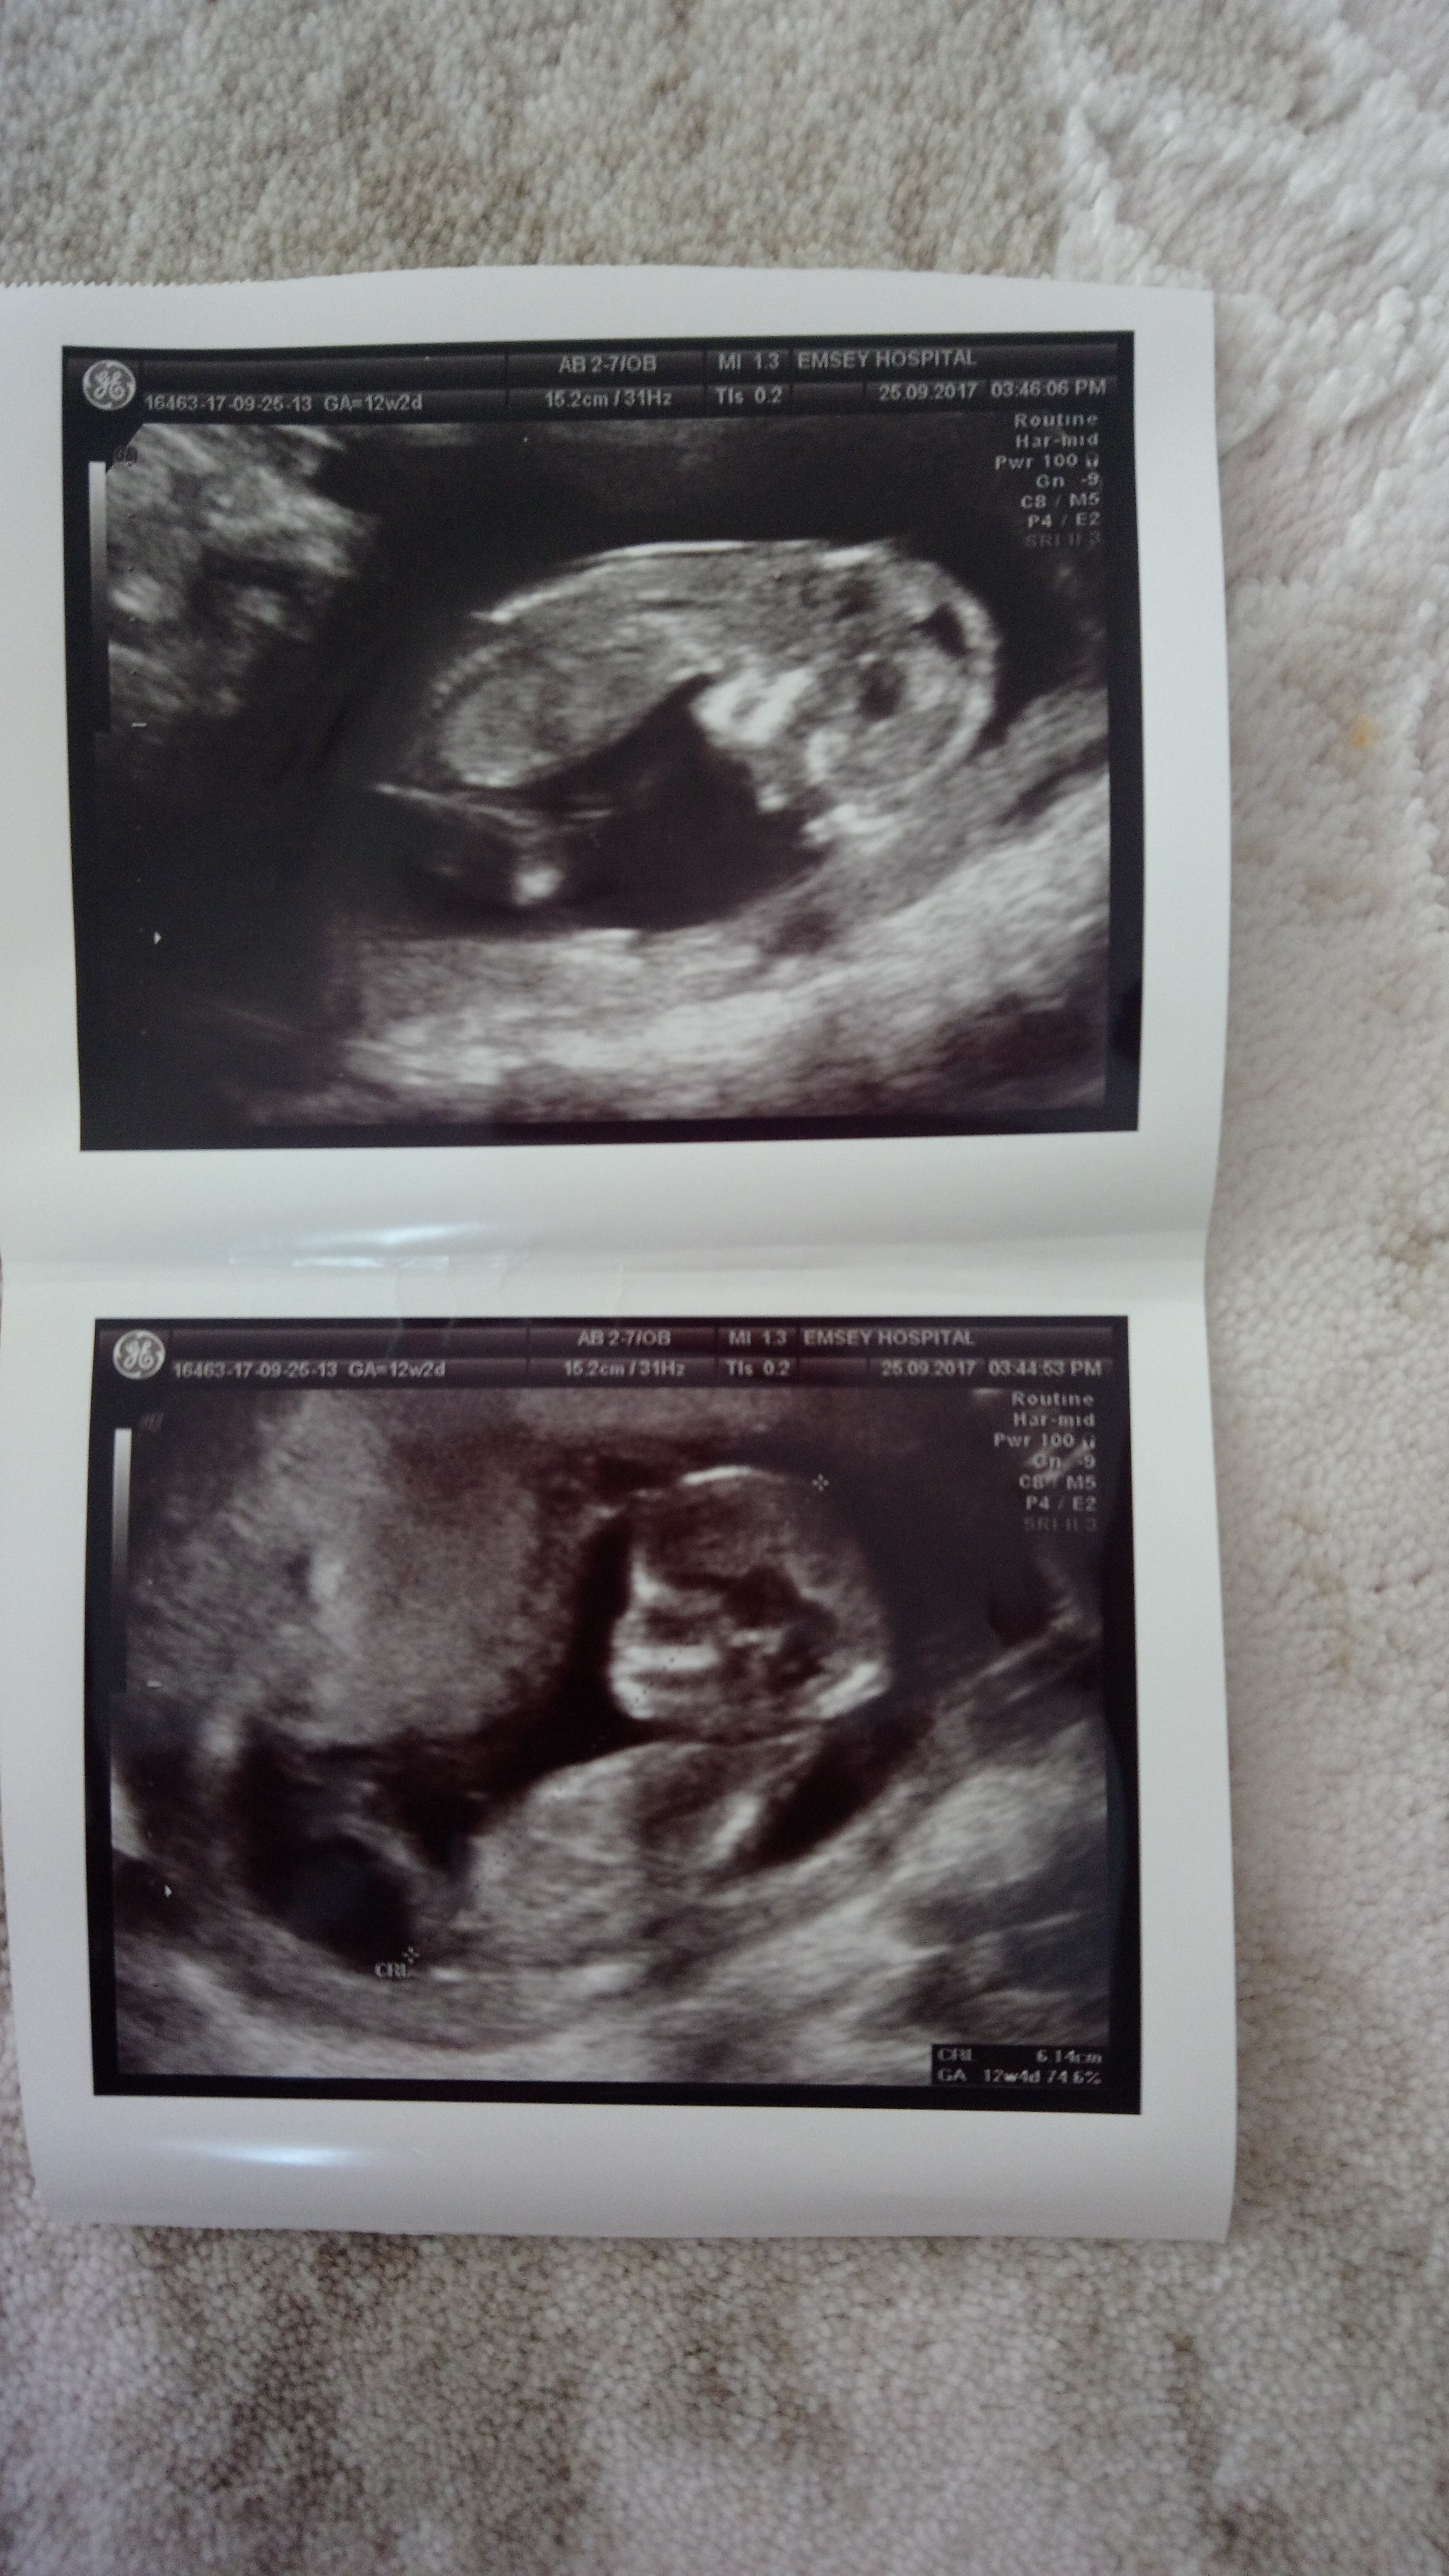

Z Zelihazeliha35 Yeni Üye Üye 25 Eylül 2017 #352 11+4 haftalık bebeğim cinsiyetini merak ediyorum tahminde bulunur musunuz? Ekli dosyalar IMG_20170922_205945.jpg 1,9 MB · Görüntüleme: 546

Uzman SühaN Administrator 25 Eylül 2017 #353 Merhaba, yüklediğiniz görselde nub çıkıntısı belli değil. Bu yüzden değerlendirme yapamıyoruz..